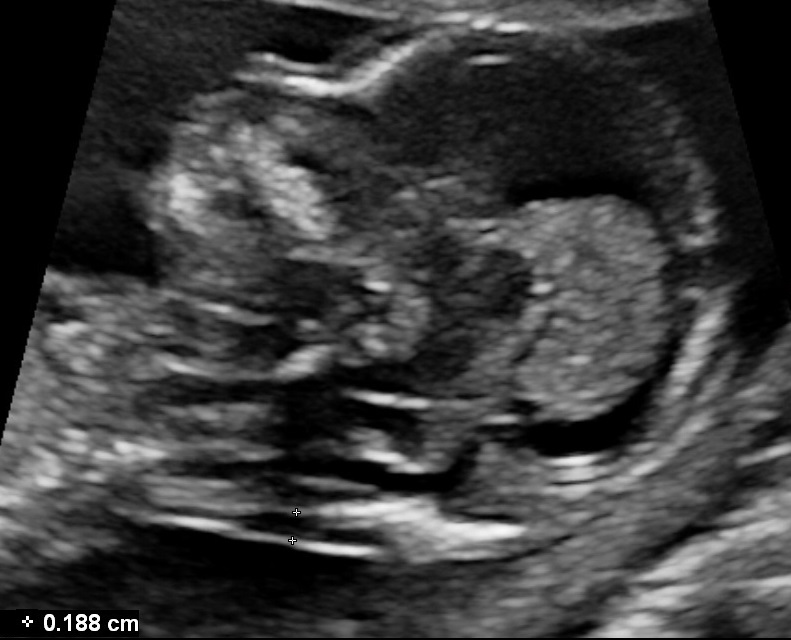

- Medial view of the fetal face in a true sagittal section of the fetus, defined by the presence of the echogenic tip of the nose and rectangular shape of the palate anteriorly, the translucent diencephalon in the center and the nuchal membrane posteriorly.

- Calipers should be placed on-on to measure NT as the maximum distance between the nuchal membrane and the edge of the soft tissue overlying the cervical spine.